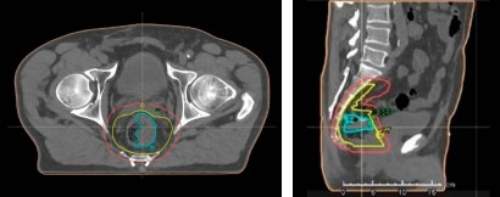

Завдяки великій апертурі гентрі Aquilion Exceed LB дозволяє легко позиціонувати пацієнтів з винятковою точністю. Потужні технології візуалізації на основі штучного інтелекту та передові функції, що враховують особливості лікування, дозволяють ефективно організувати робочий процес у галузі радіаційної онкології без шкоди для пацієнта, якості зображення та клінічної цінності.

Комплексна ідентифікація цілей і контурування органів з злоякісними новоутвореннями є ключовим для успішного проведення променевої терапії. З огляду на це Aquilion Exceed LB дозволяє виконанувати високоякісні КТ-дослідження з низькими дозами, які забезпечують чітке уявлення про локалізацію пухлин і дозволяє оптимізувати моделювання точного положення для високоточного планування терапії.